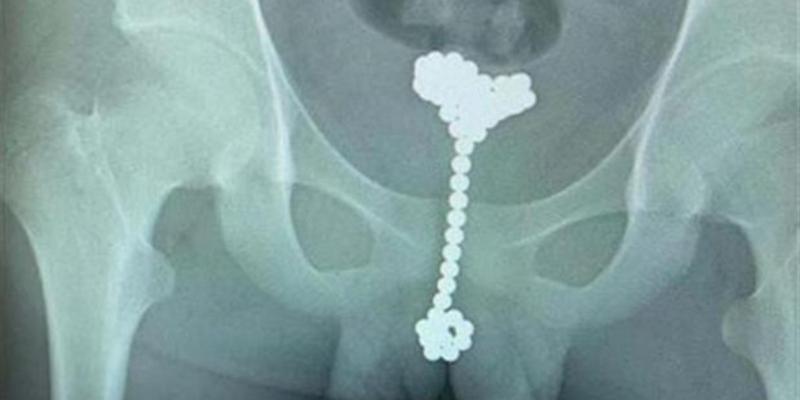

Dos jóvenes se introdujeron 84 bolas magnéticas por el pene para explorarse

En los últimos meses, el hospital infantil de la ciudad china de Wuhan ha diagnosticado dos casos llamativos e inusuales. Y es que dos adolescentes sin relación alguna han tenido que ser atendidos tras introducirse por el pene bolas magnéticas con el fin de 'explorar el cuerpo humano'.

El médico jefe del departamento de urología le extrajo un total de 53 bolas

La semana pasada, un adolescente de 14 años acudió al hospital a causa de una hemorragia que él mismo se había provocado. El menor se habría metido dos hileras de bolas magnéticas por el pene "por curiosidad".

Tal y como informa el medio chino «Chutian Metropolis Daily», el menor se introdujo una hilera por la uretra. Pero después de notar molestias, intentó extraerla con otra hilera similar y no fue posible. Y aunque sentía dolor, el chico prefirió callarse por vergüenza. Fue al día siguiente cuando tuvo que ser operado de urgencia a raíz de la hemorragia desarrollada.

A otro adolescente le sacaron 31 bolas del pene

Poco después, otro adolescente de 13 años fue llevado al hospital por sus padres al sufrir "fuertes dolores abdominales". Allí, los médicos descubrieron que el menor tenía 31 bolas magnéticas dentro del pene.

El joven, que se sentía avergonzado, explicó que trataba de "explorar el cuerpo humano". Entonces reveló que las pequeñas bolas llevaban algo más de dos meses en el interior de su organismo.

Según el servicio médico, en ambas operaciones se usaron "cirugías de vejiga de gas mínimamente invasivas". Sin embargo, en el segundo caso los médicos optaron por llenar la vejiga del menor con aire para poder extraer las bolas sin necesidad de una operación más compleja.